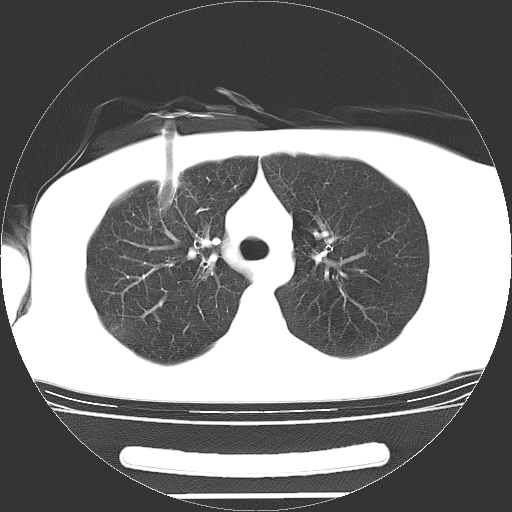

标题: CT19767:男,20岁,右侧气胸行闭式引流术后五天CT检查。 [打印本页]

男,20岁,右侧气胸行闭式引流术后五天ct检查看肺内是否有肺大泡,纵隔窗未见异常,未上传。

1)右侧胸腔闭式引流术后导管留置。2)右肺未见肺大泡。

未见肺大泡,还有微量气体。